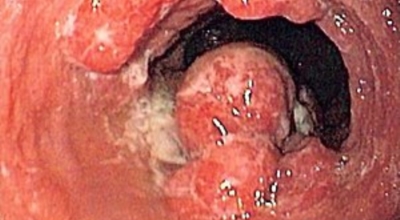

식도 점막이나 표피해 암이 있을 경우 음식물을 삼킬 때마다 통증이 있을 수 있어요. 목감기도 아니고 역류성 식도염도 아닌데 음식물을 삼킬 때마다 통증이 있으면 식도암 초기증상을 의심해보세요. 목이 까끌까끌하고 부드러운 목넘김이 없다면 분면 식도 어딘가 문제가 있는 거에요. 입하고 가까운 식도는 육안으로도 넉넉하게 식별이 가능함으로 가까운 이비인후과나 내과에 방문해보세요.

식도암은 다른암에 비해 사망률이 아주 높은 암이랍니다. 초기 발견 시에는 예후가 매우 좋지만, 2,3기에 발견될 시에는 사망률이 급격히 오르게 돼요. 다만 초기에는 증상이 거의 없으므로 문제가 됩니다. 초기에 관찰되는 경우는 내시경을 통한 방법말고는 거의 없다고 합니다. 그러기에 주기적인 내시경은 필수겠죠.

안타깝지만 식도암 초기증상은 잘 느끼지 못합니다. 하지만 방법은 있어요. 그것은 바로 위 내시경 검사를 받는 것으로 보입니다. 위 내시경 검사를 받을 때 식도를 거쳐서 내시경 검사를 하므로 우리는 반드시 2년에 한번씩, 나이가 50대가 넘었다면 1년에 한번씩 내시경 검사를 받아야 합니다.